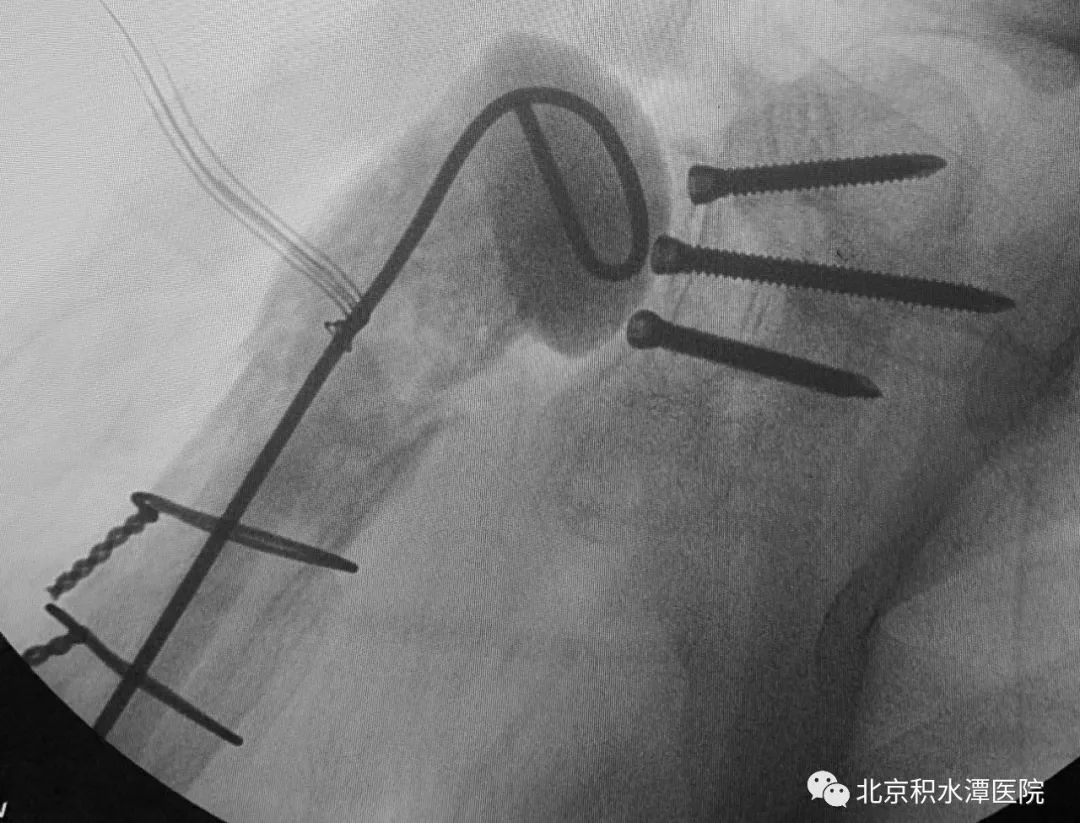

首先行假体取出、扩创控制感染,后期再行反肩关节置换。完善相关检查后,于2018年5月手术,扩创取出原假体,抗生素骨水泥植入。术中最大的难点在于肱骨侧假体、骨水泥及髓腔塞取出困难,而任何残留都可能会造成感染复发,术中采用肱骨干纵行劈开方式将假体、骨水泥和髓腔塞全部取出,并用钢丝捆扎修复,而肩胛盂侧的假体取出则较为顺利,但患者大小结节均已移位,肩袖组织完全挛缩。术后培养为表皮葡萄球菌,通过抗生素治疗,患者的感染顺利控制。